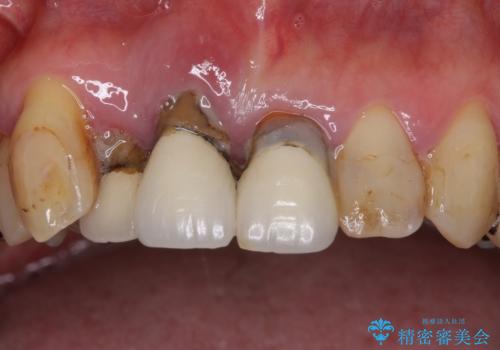

①保存不可の歯の抜歯・根管治療

②矯正治療

③セラミックの装着

という流れで行いました。